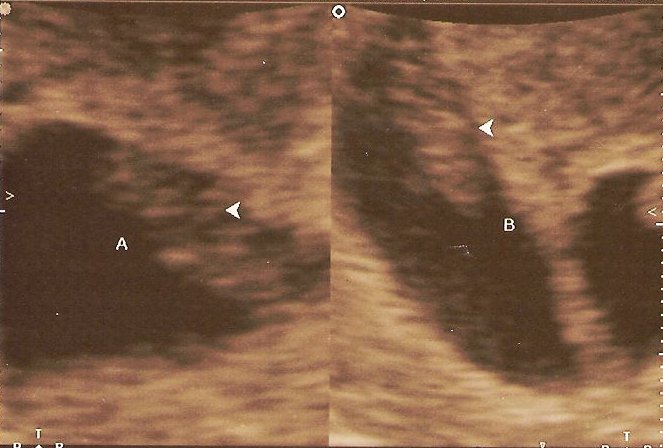

Regina had an appointment with the baby doctor at 8:00 AM yesterday. The nurse operating the ultrasound machine told us she would first look at the top of her stomach before looking at the babies closeup (at 8 weeks, they would be the size of kidney beans). Then she told us something we were not expecting, or prepared for. Regina is carrying TWINS!!!! Both of our jaws had to be picked up off the floor. My eyes were watering, and my head was spinning. The nurse then went in for a closer view to do the measurements, heart rate, etc. These pics are from the closeup view. Even at this small size we could easily see their heart beat. The twins are due November 29, 2007.